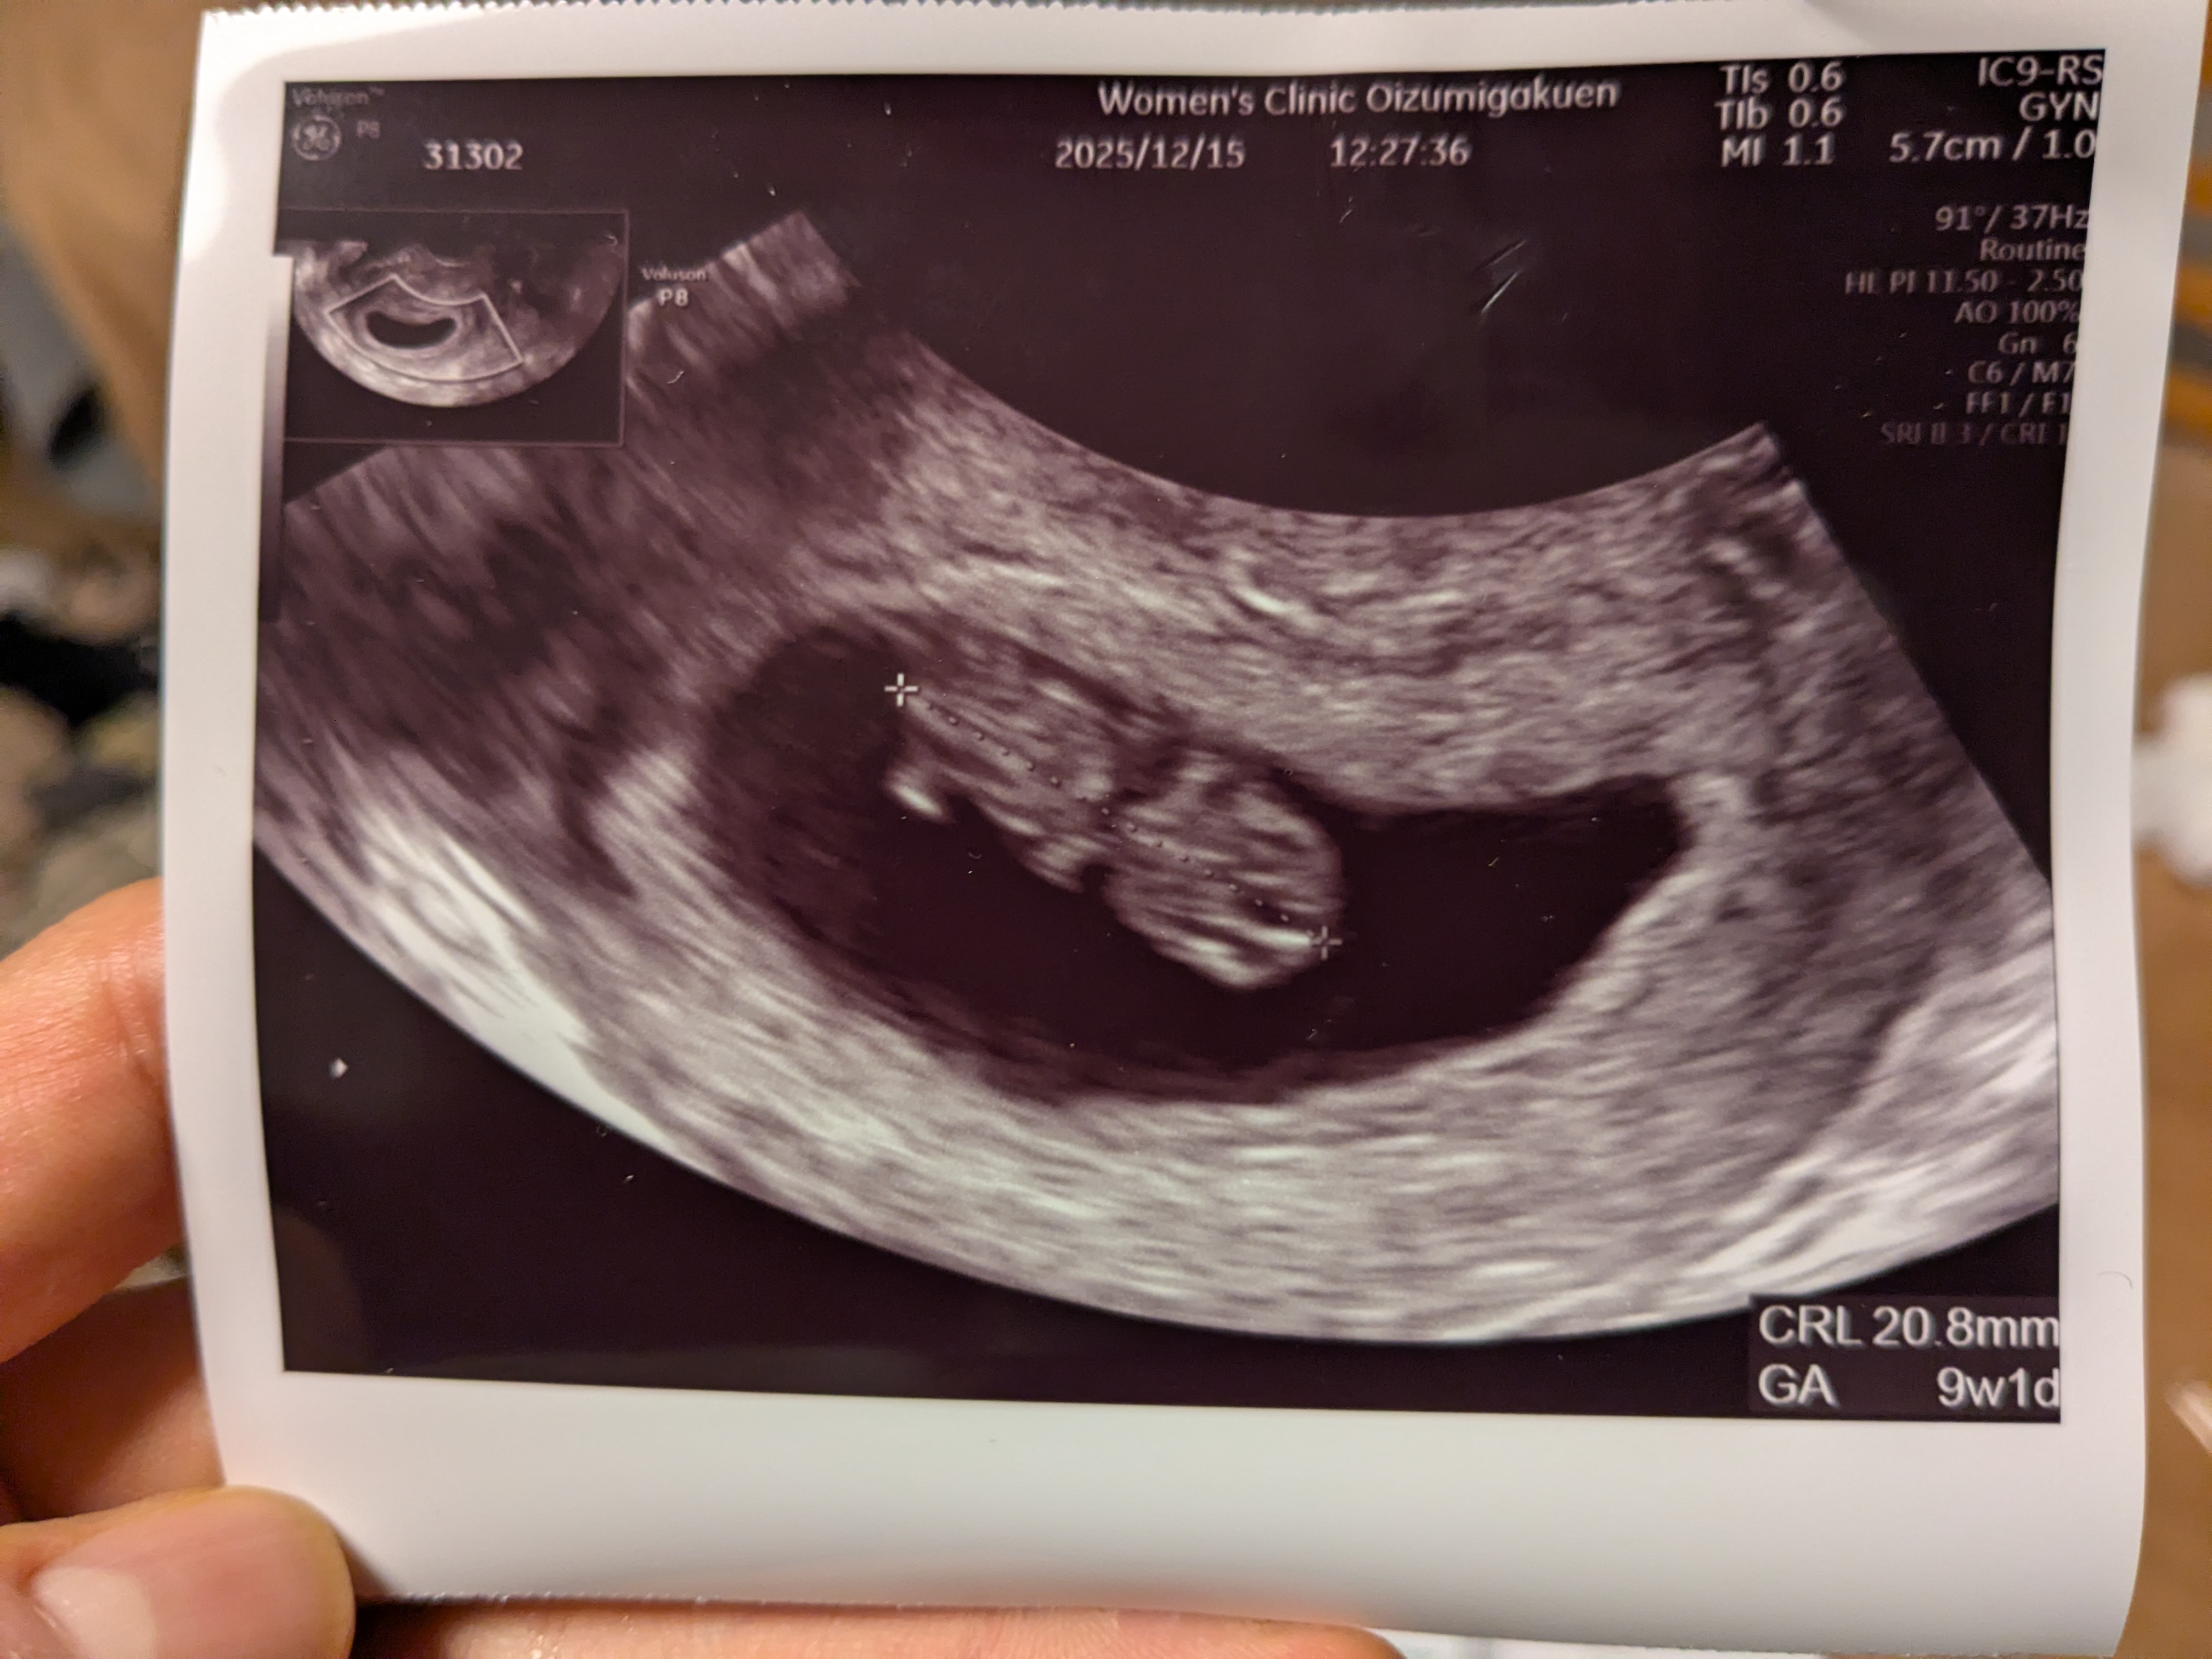

今日は遂に2週間ちょっとぶりの検診へ!

たつくんは仕事のため、やに一人で病院へGo。

しかし落ち着かず、結局たつくんも病院へGo。

二人でドキドキしてエコー検査を待つ。

そして結果、無事に育ってて心拍も聞こえた!

これにて不妊治療は卒業で、いよいよ転院の準備。